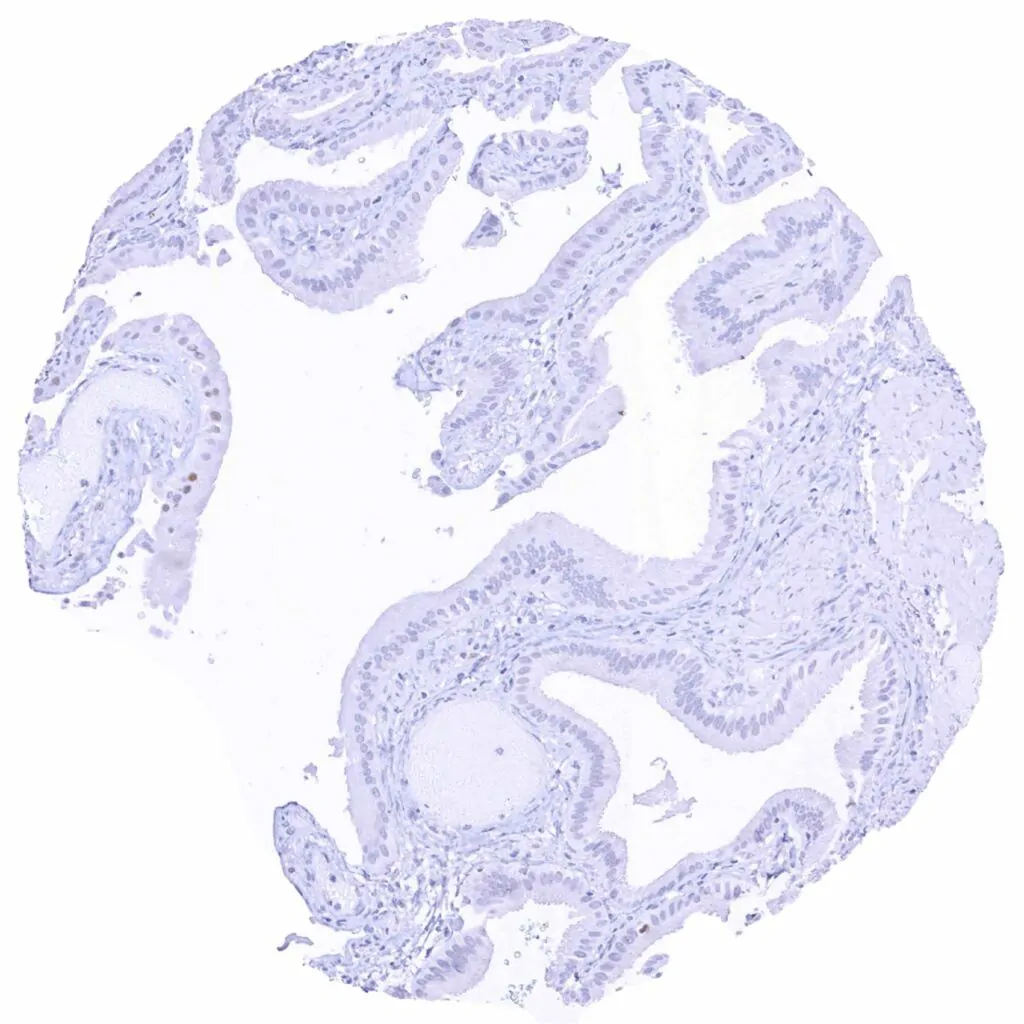

Gallbladder, epithelium – Lack of Cyclin E1 staining in this sample

Gallbladder, epithelium – Weak Cyclin E1 staining of only few epithelial cells